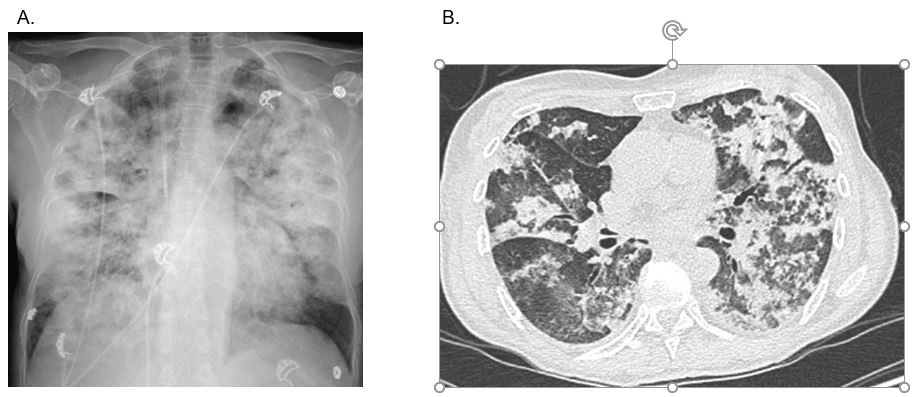

A. Radiographie pulmonaire montrant des condensations alvéolaires diffuses

B. Scanner en coupe transversale montrant des condensations mixtes avec part de verre dépoli intéressant les différents lobes de manière diffuse et non systématisée.